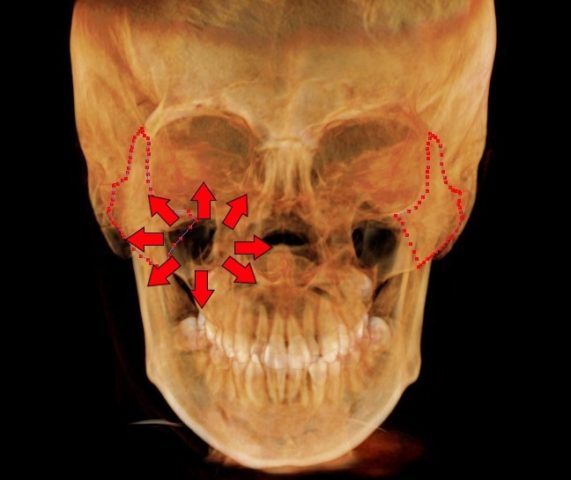

頬骨 痛いとき 急性上顎洞炎の治療

慢性上顎洞炎が、突然、急性化し、

顔が痛いし、頬骨も痛いほどの

急性上顎洞炎がおきました。

緑矢印 正常な上顎洞

黄矢印 膿がたまっている上顎洞

赤矢印 原因になった歯根

(上顎洞の底の骨が、溶けています)

仕事も休まれました。